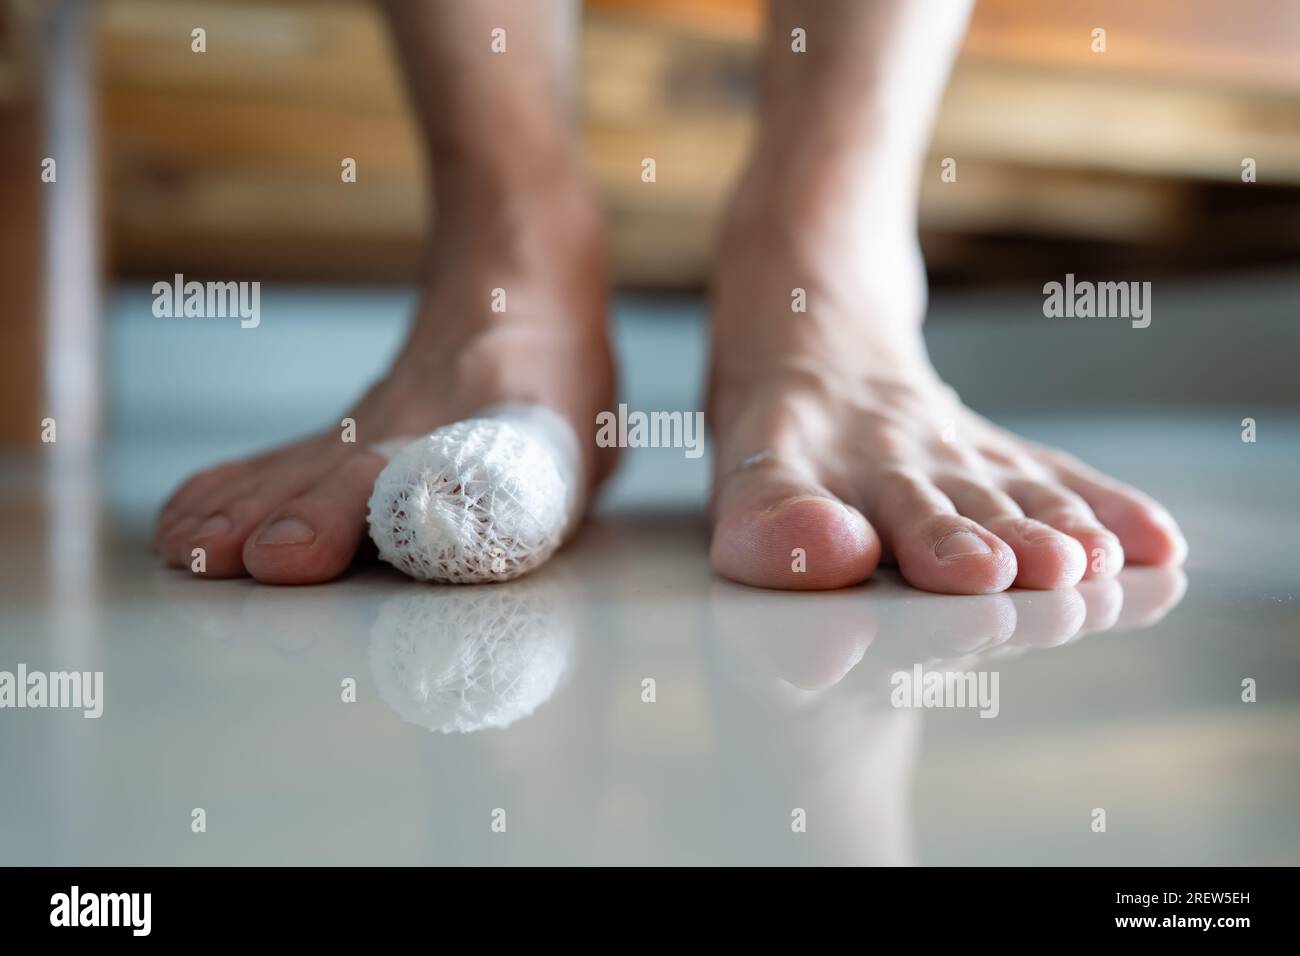

RF3B12YK2–Eine Nahaufnahme der Füße zeigt signifikante Schwellungen und Blutergüsse am linken Fuß aufgrund einer Zehenfraktur, im Gegensatz zu einem gesunden rechten Fuß.